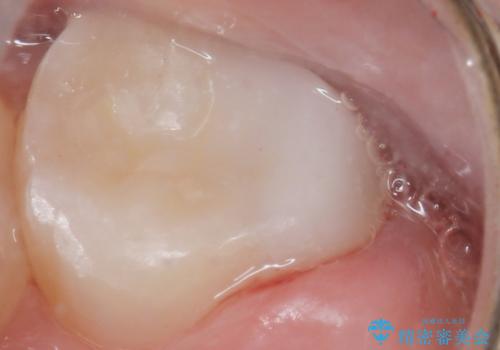

患者様のご希望により、う蝕を丁寧に除去したのちセラミックインレーによる修復を行いました。

審美的な仕上がりと自然な咬み心地にご満足頂けました。

インレーの種類:セラミックインレー(e-max press)